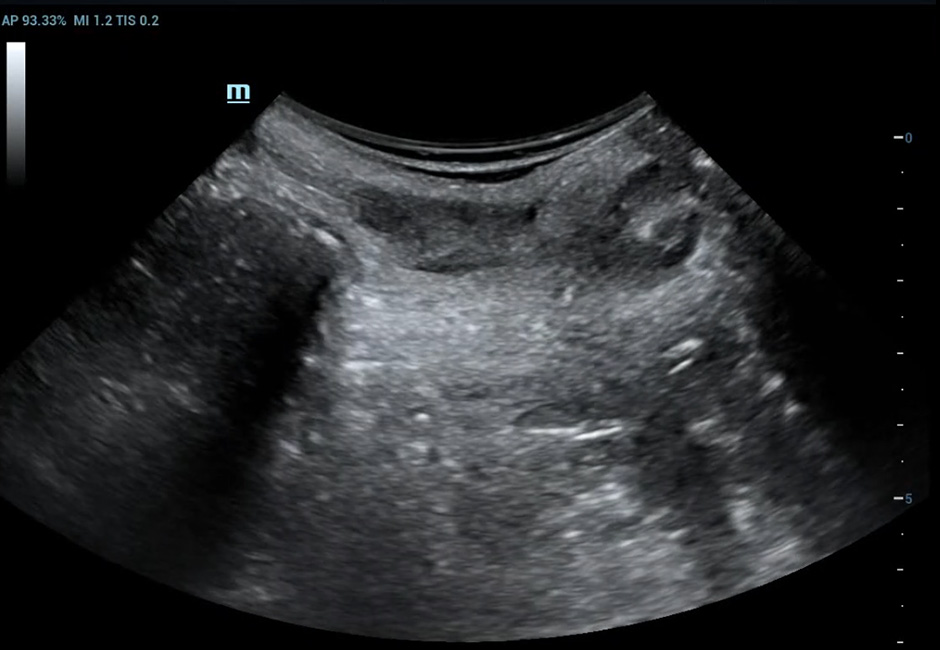

Rectocele